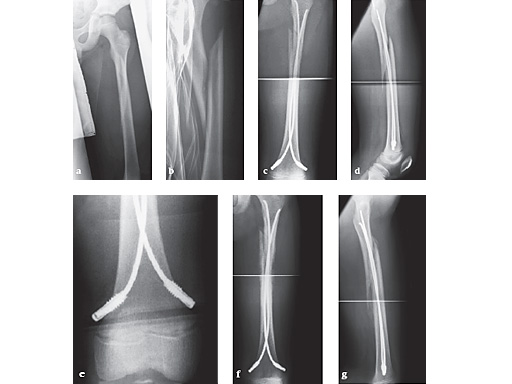

Case 1

Case of a 8-year old boy with a closed lower leg fracture after football game.

Fig 13a-b: X-rays show a long spiral fracture of the proximal third of the right femur (32D/5.1). Because of the age good indication for ESIN, but some danger of instability is possible.

Fig 13c-d: Postoperative x-rays. A closed reduction and fixation with 3.0 mm TEN was carried out with correct child-oriented alignment. For stability reasons two End Caps became uses. No signs of a shortening can be seen.

Fig 13e-f: AP and lateral view 6 weeks after surgery shows good callus formation and still a perfect alignment.

Full weight bearing was then allowed.